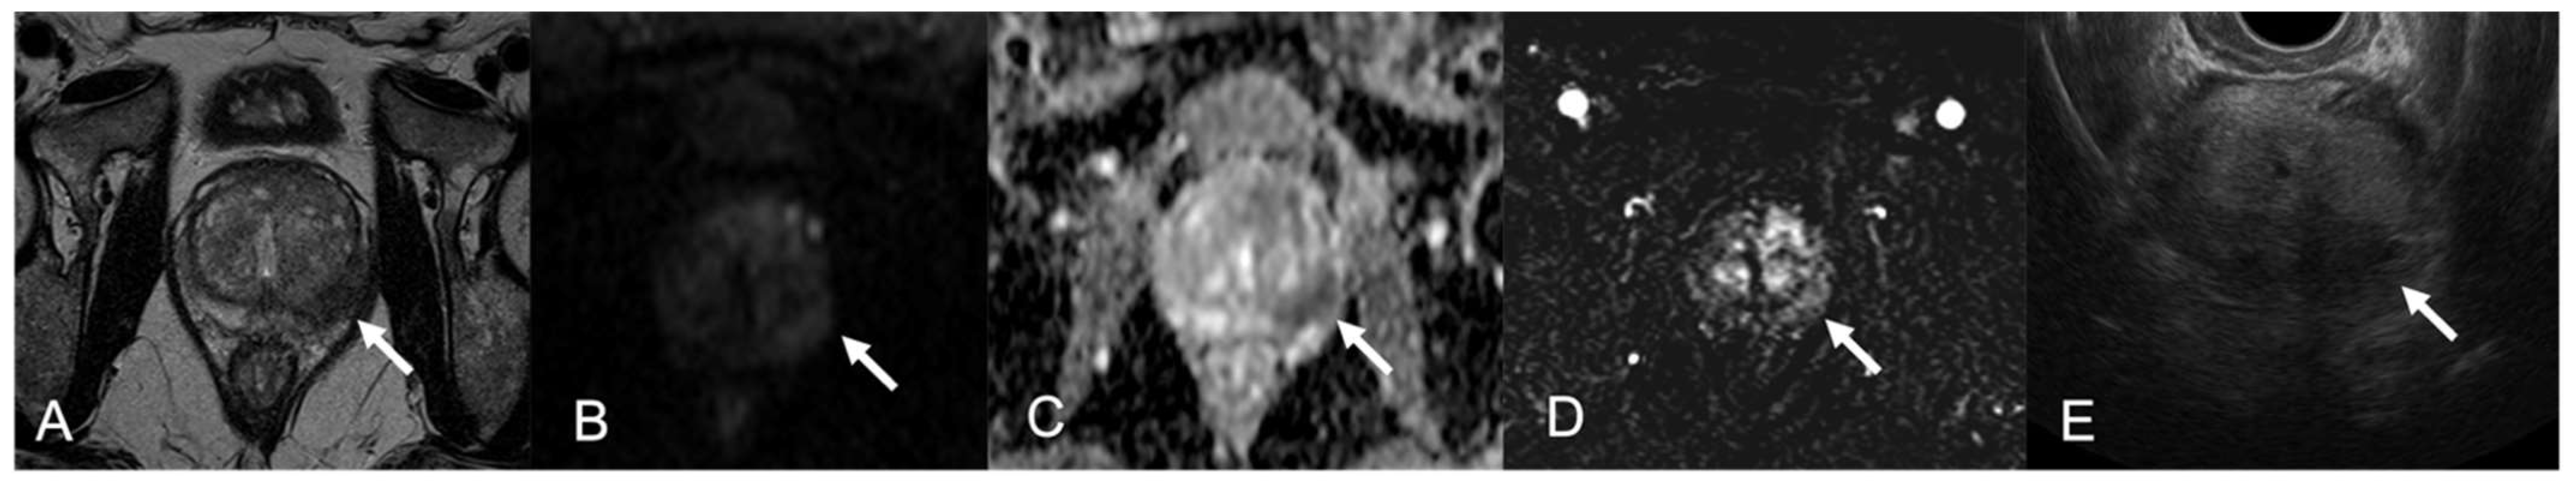

| 6 | PZ diffuse (index lesion PZpm mid-base left; TZa base right | Confluent pseudonodular hypointense areas, capsular bulging; 2-cm marked hypointense irregular TZ lesion | Marked hyperintense; hyperintense | Marked low ADC value; Marked low ADC value | Peripheral rim enhancement and avascular core in the index lesion; inhomogeneous, intense and prolonged enhancement | 5; 5 |

| 8 | PZpm mid-base left | Markedly hypointense nodule, focal capsular bulging | Marked hyperintense | Marked low ADC value | Peripheral rim enhancement, avascular core | 5 |